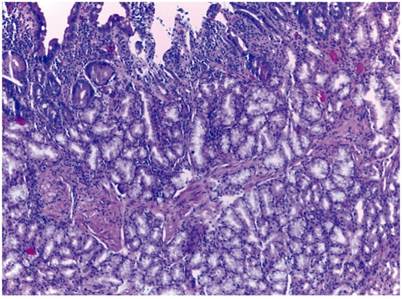

En el estudio histológico de la lesión se observa proliferación de glándulas submucosas, por lo que se diagnostica hiperplasia de glándulas de Brunner (Figura 2). La tomografía computarizada (TC) mostró ausencia de extensión extraluminal. Dado el pequeño tamaño de la misma, el origen iatrogénico de la hemorragia y la ulterior ausencia de sintomatología se decide actitud expectante y el paciente permanece asintomático 8 meses después del diagnóstico.